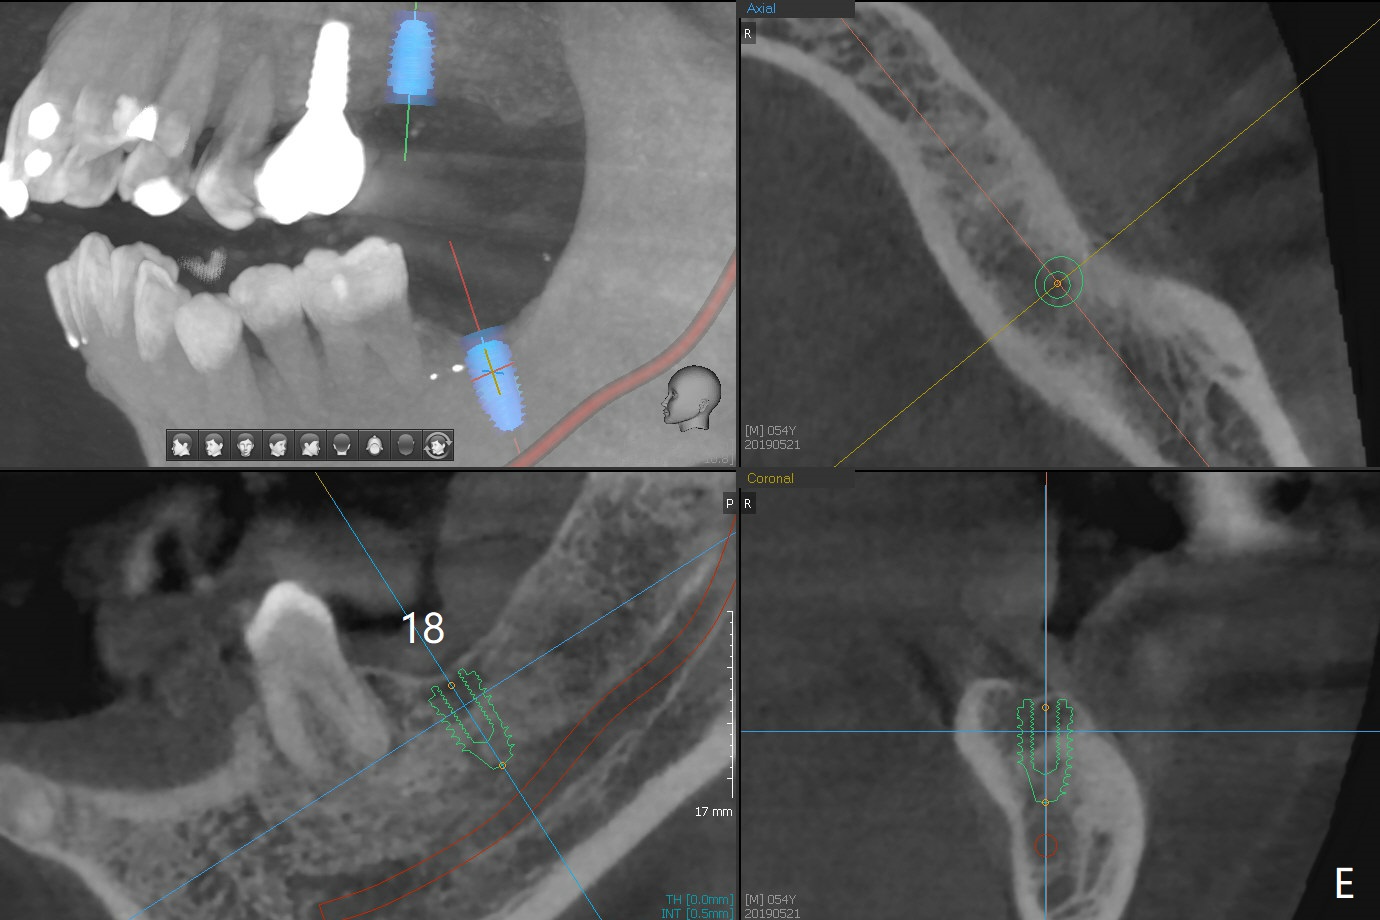

A 54-year-old man remains difficult in mastication in spite of implant placement at #14 and 31 (Fig. A, B, E, including screw loosening (poor trajectory at #14)). In addition to 2 more implants at #15 and 18 with guide, malocclusion seems to be necessary to be addressed (Fig.1-5). It appears that UR, LL4 should be extracted for orthodontic treatment (Fig.6-10). To reduce screw loosening, IS guide will be used to place IBS (5x9mm) and tissue-level (5x11mm) implants at #15 (PRF)and 18, respectively. If the one at #14 or 15 keeps loosening, splint #14 and 15 crowns. In fact the patient agrees with limited ortho (UR7 cross bite).